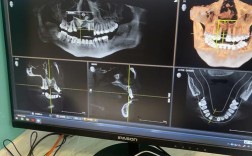

- 精确的术前影像学评估(CBCT)是必须的,确定颏孔和下牙槽神经管的确切位置。

- 术前评估: CBCT确定骨量、神经血管位置、颏孔位置,评估牙龈厚度和生物型。

- CBCT是术前规划不可或缺的工具,用于精确评估骨量和神经位置。